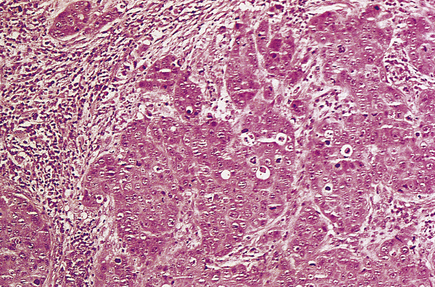

Medullary carcinomas are circumscribed and often large. Histologically, they are composed of large tracts of confluent cells with little stroma in between them. The cells show quite marked nuclear pleomorphism, and mitotic figures are frequent. There is never evidence of gland formation. These cytological appearances put them into the ‘poorly differentiated’ category. Around the islands of tumour cells there is a prominent lymphocytic infiltrate, predominantly T-lymphocytes, with macrophages (Fig. 18.26).

image

Fig. 18.26 Medullary carcinoma. Large groups of irregularly shaped tumour cells are surrounded by an infiltrate of lymphocytes.

Despite the aggressive cytological features of these tumours, the patients have a significantly better 10-year survival than women with invasive duct carcinomas. It may be that the lymphocytic and macrophage infiltrate has a beneficial effect, and this has stimulated much research into the immunological responses to tumours generally.